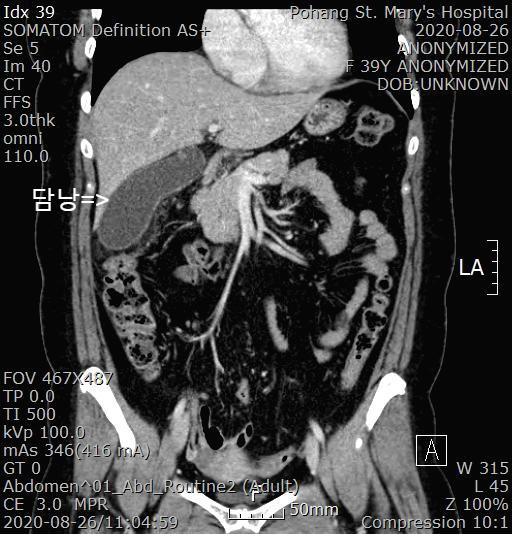

복부 CT를 진행했습니다.

복부 CT 판독 소견

GB distension & wall thickening with pericholecystic fat stranding

---> Acute cholecystitis, suggested

담낭이 염증으로 부풀어 있고 담낭벽도 두꺼워져 있습니다. 급성 담낭염에 합당한 소견입니다.